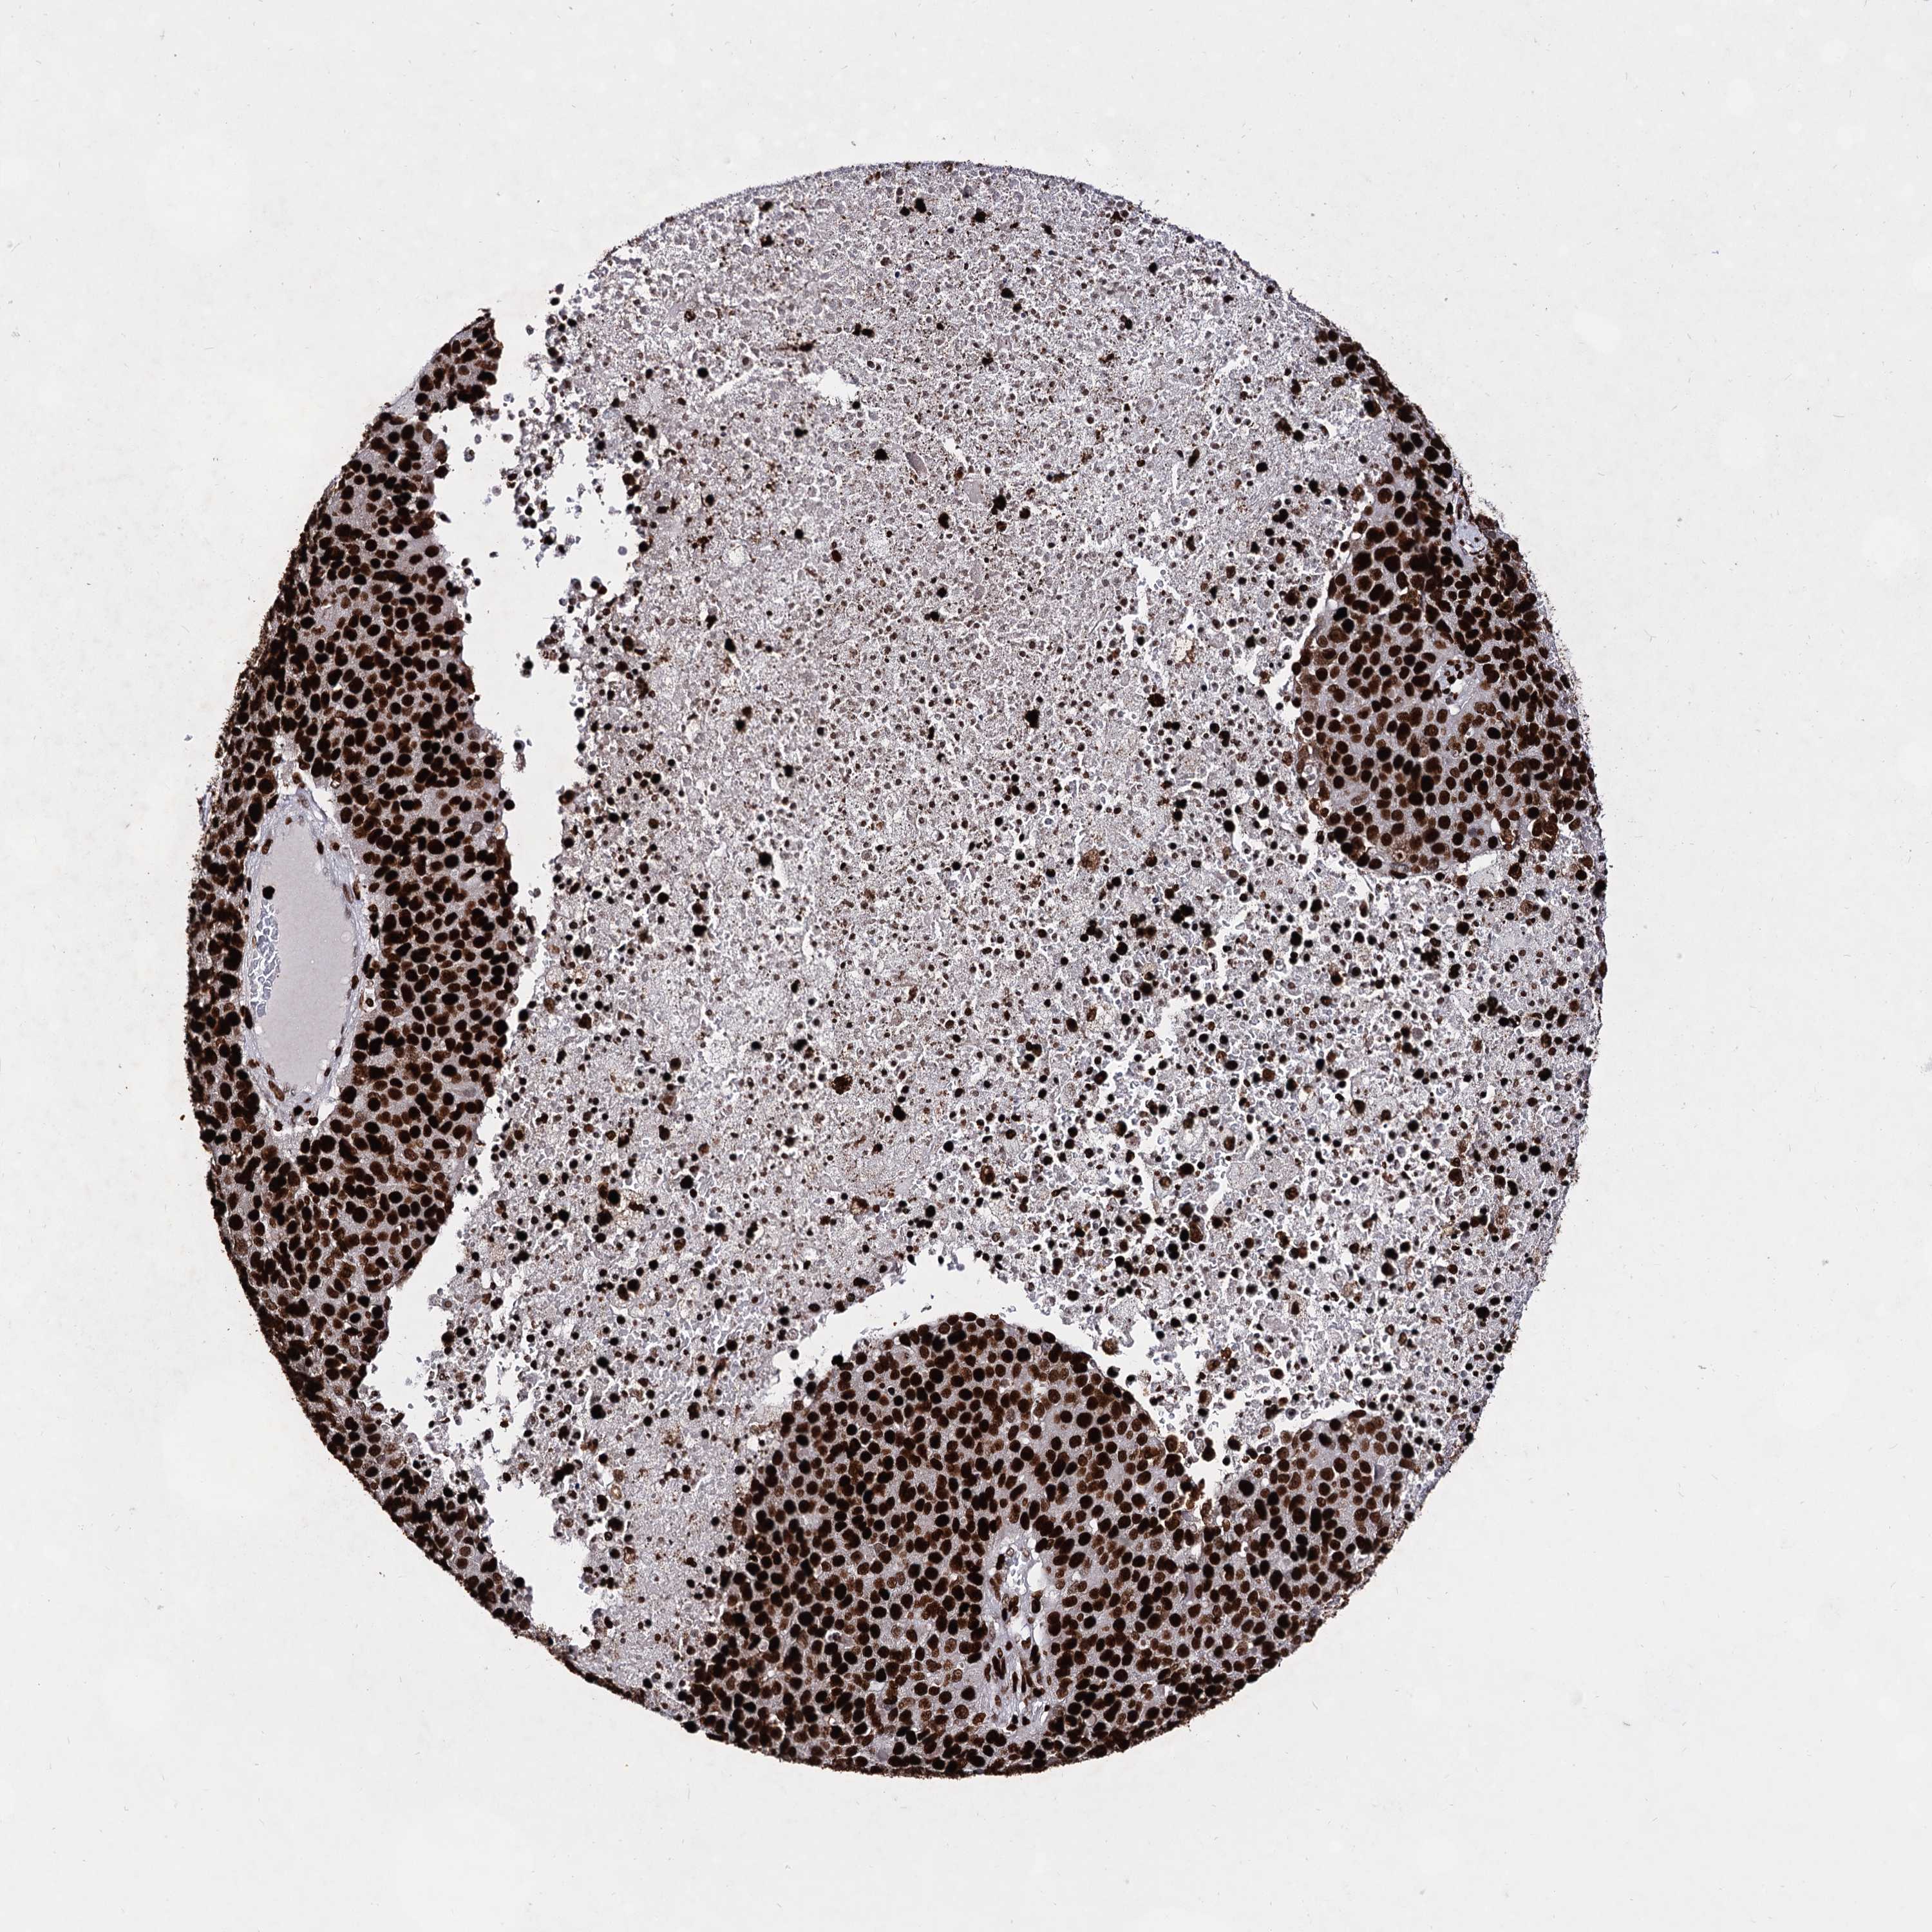

PANCREATIC CANCER - Protein expressioni

A mouse-over function shows sample information and annotation data. Click on an image to view it in a full screen mode. Samples can be filtered based on level of antibody staining by selecting one or several of the following categories: high, medium, low and not detected. The assay and annotation is described here.

Note that samples used for immunohistochemistry by the Human Protein Atlas do not correspond to samples in the TCGA dataset.

Antibody stainingi

Antibody staining in the annotated cell types in the current human tissue is reported as not detected, low, medium, or high, based on conventional immunohistochemistry profiling in selected tissues. This score is based on the combination of the staining intensity and fraction of stained cells.

Each image is clickable and will lead to virtual microscopy that enables deeper exploration of all samples and also displays staining intensity scores, fraction scores and subcellular localization as well as patient and tissue information for each sample.

Antibody HPA003506

Antibody HPA053314

Antibody CAB037206

Staining

High

Medium

Low

Not detected

Intensity

Strong

Moderate

Weak

Negative

Quantity

>75%

75%-25%

<25%

None

Location

Nuclear

Cytoplasmic/membranous

Cytoplasmic/membranous,nuclear

Adenocarcinoma, NOS